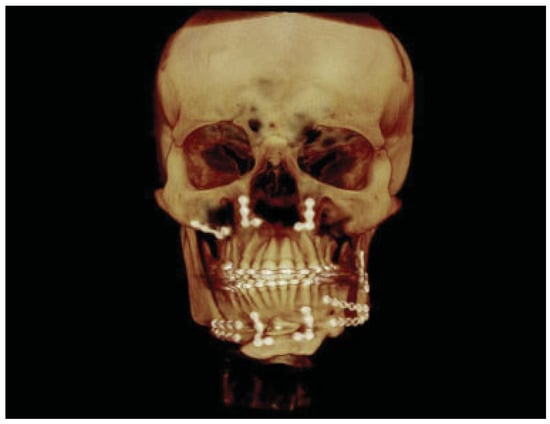

:Case Report